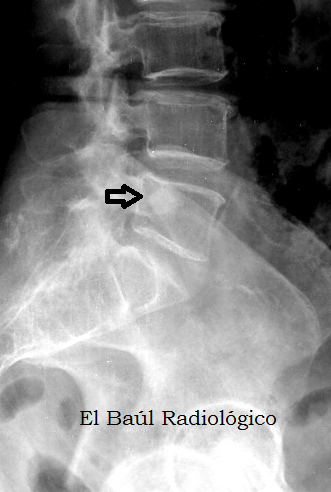

FIGURA 2) El islote óseo también se aprecia en una radiografía convencional de la columna.

(The bone island is also seen in a conventional radiography of the spine).